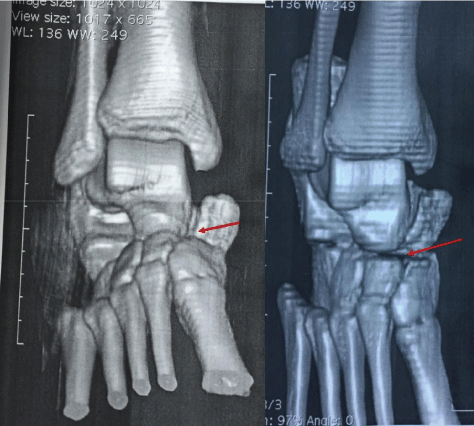

A right foot/ankle X-ray requested and a CT scan showed a medial dislocation of the talonavicular joint without fracture (Figure 1a and Figure 1b).

Figure 1A: An X-ray view of the right Ankle showing a medial luxation of the talonavicular joint (red arrow). View Figure 1A

Figure 1B: A CT scan view of the right ankle/foot showing a medial luxation of the talonavicular joint. View Figure 1B